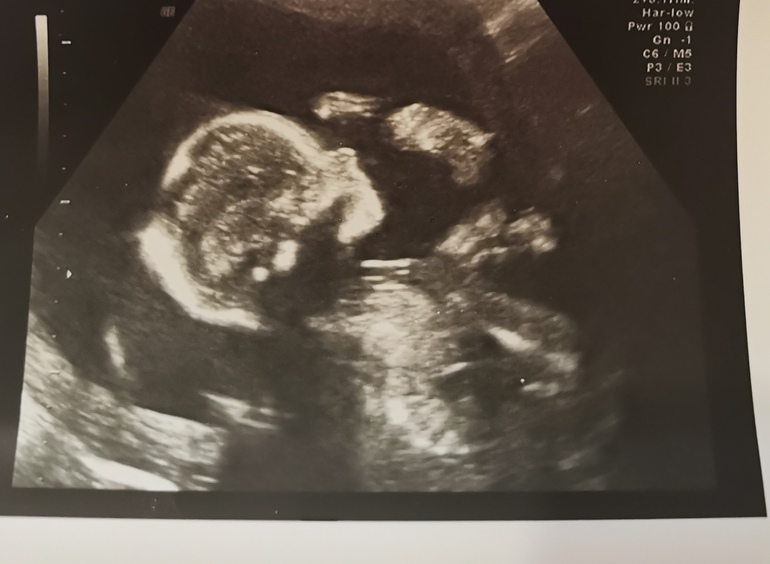

2 скрининг пройден. ❤️ЭКВАТОР❤️

Вот и пройден наш 2 скрининг. С малышкой все хорошо. Выдыхнули. Все-таки диагноз краевое предлежание. Эх. Теперь контроль узи у гинеколога. Но самое важное, что девочка наша растёт. Опережаем на неделю. По месикам нам 20 ровно. А по узи поставили 21 неделю. Теперь будем беречь себя. Девочки у кого краевое ставили на этом сроке, плацента поднялась или нет?